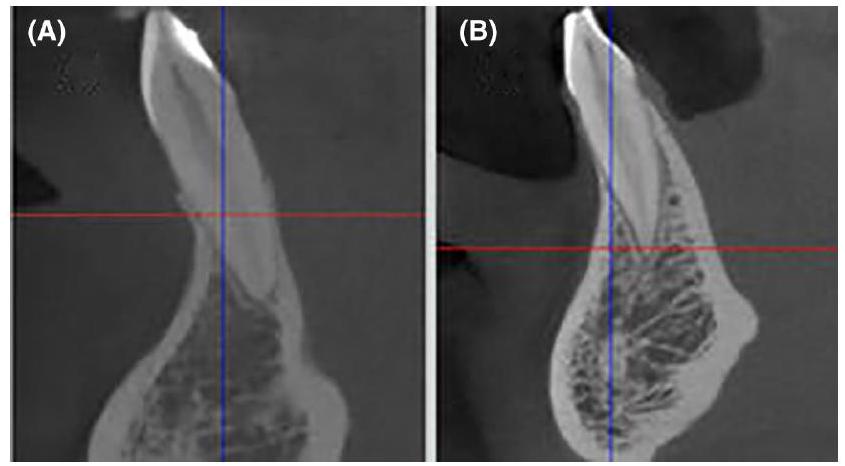

- Domic D, Bertl K, Ahmad S, Schropp L, Hellén-Halme K, Stavropoulos A. Accuracy of cone-beam computed tomography is limited at implant sites with a thin buccal bone: a laboratory study. J Periodontol. 2021;92:592-601.

in CBCT-based assessment of tiny structures in the submillimeter range will be beset with a significant margin of error. This is supported by the observations of Domic and colleagues who found a detection accuracy of only